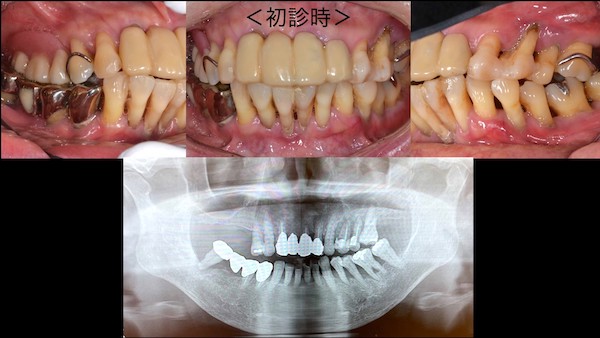

①歯周病の検査、治療説明

歯周病がかなり進行していたため、まずは検査から始めました。重度の歯周病で保存が難しい歯に関しては、抜歯することを説明しました。また、既に歯がない部分に関しては、入れ歯・ブリッジ・インプラント治療の3つの方法を提示し、メリット・デメリットを詳しくお伝えしました。